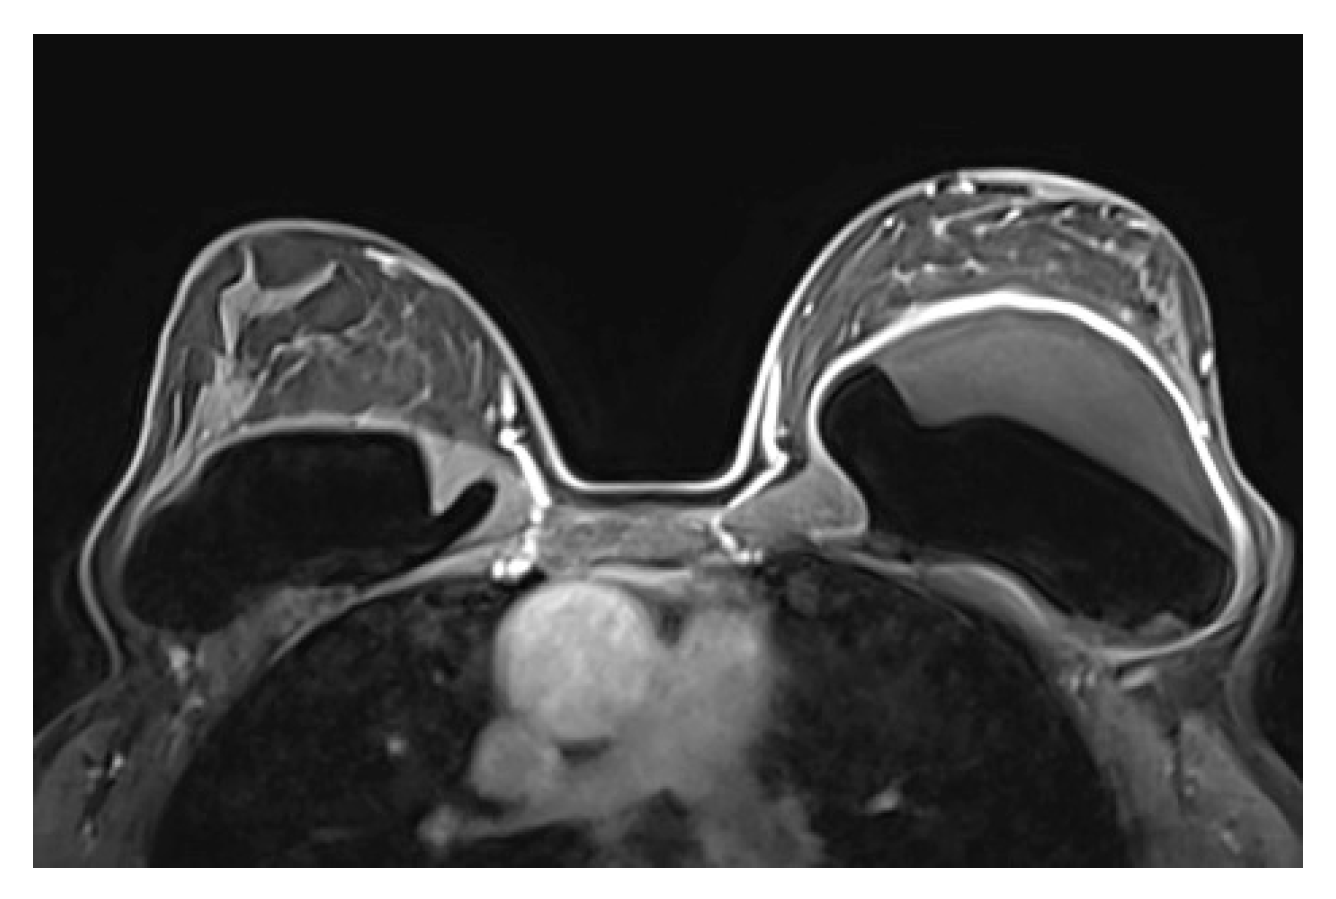

A single lumen implant has an intact shell and is surrounded by a thin fibrous capsule with low signal intensity on all sequences. Saline implants appear with water signal intensity on all sequences, and a valve is recognized within the lumen with low signal intensity, while silicone implants show high signal on T2-weighted and silicone-selective sequences and low signal on T1-weighted sequences (Figure 4). A double lumen implant appears with an inner chamber of silicone with high signal intensity and an outer chamber of saline with water signal intensity (Figure 5) [47,49].

Internal radial folds and a small amount of peri-implant reactive fluid are normal findings [27,48]. Radial folds are infoldings of the shell extending from the periphery of the implant, usually as a result of implant contracture and are characterized as simple when they are short and straight, and complex that are longer and curved that may mimic an intracapsular rupture (Figure 6). Radial folds have a sheetlike appearance and a more perpendicular orientation to the imaging axis, while the rupture is more parallel. It is important to review multiple sequential images on all planes in order to recognize the folds communicating with the shell and differentiate them from intracapsular rupture [50].